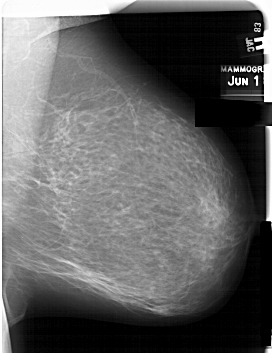

A_1560_1.RIGHT_CC

RIGHT_CC LINES 6871 PIXELS_PER_LINE 4636 BITS_PER_PIXEL 12 RESOLUTION 43.5 NON_OVERLAY